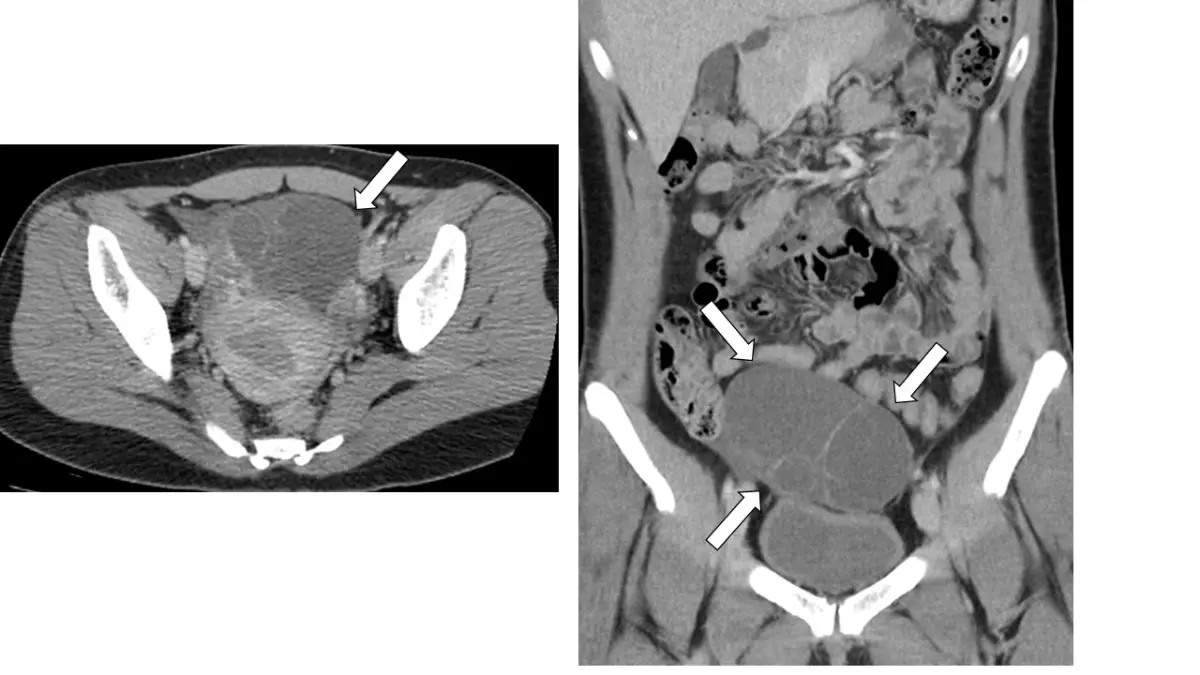

37歲女性,下腹部電腦斷層檢查呈現如圖,箭號所指之敘述何者最為可能?

- 從橫斷面(axial)及冠狀面(coronal)對比增強CT可見一巨大多房性囊性腫塊位於骨盆中央,與子宮、膀胱明顯分離,呈均質低密度(近水樣)

- 各房室由極為薄且平滑的分隔連接,分隔壁無明顯厚度不均或結節增生

- 無任何脂肪成分(低HU區)、鈣化或實質造影增強結節

- 腫塊可擠壓並取代正常組織,延伸範圍可達下腹部,但與膀胱壁和子宮肌層無連續性

符合典型良性卵巢serous cystadenoma影像特徵。